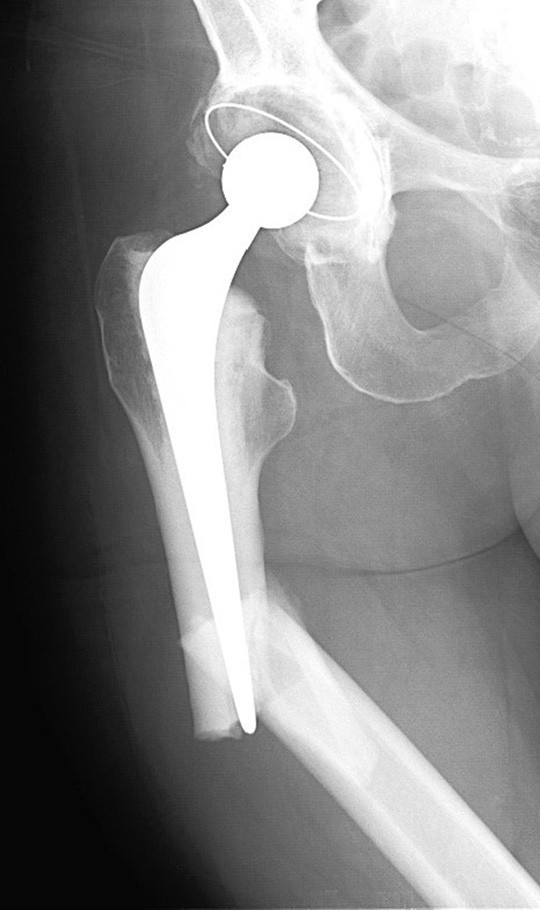

Når det gjelder femurfrakturene hos vår pasient, supplerer vi her med et preoperativt bilde av høyre femur som oppfyller kriteriene på atypisk fraktur, med frakturlinje som er i rett vinkel på femurs lengdeakse lateralt (figur 1). I figur 2 ser vi et primærbilde av venstre femur, som viser en inkomplett, atypisk fraktur.